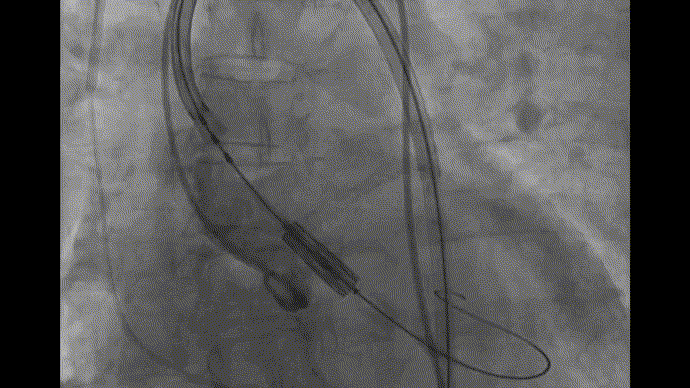

术前CT评估

图片

全主动脉入路CT评估